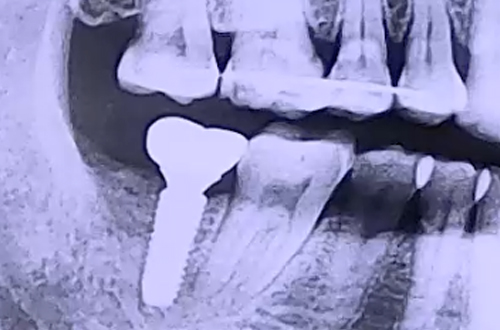

BEFORE

6개월 정도 전에 발치한 오른쪽 아래 어금니에 임플란트를 하기 위해

저희 병원에 내원해 주셨던 환자분이십니다.

발치하신 자리의 잇몸뼈 상태는 아주 좋았기 때문에

임플란트 식립에도 문제가 없는 심플한 케이스였는데요.

발치했던 어금니와 맞닿는 위 어금니가 흔들거리고 있었습니다.

비어 있는 공간 탓에 중력의 힘을 받으며 이가 약해지고

아래로 점점 내려오고 있었기 때문인데요.

임플란트가 굳기를 기다리는 동안 윗니가 내려오게 될 가능성을 고려하여

윗니를 잡아 줄 와이어를 앞쪽 치아와 이어 붙여드렸습니다.

임플란트가 굳기까지 3개월을 기다린 뒤 보철을 완성해드렸고,

윗니도 더 내려오지 않아 문제 없이 치료를 마무리할 수 있었습니다.